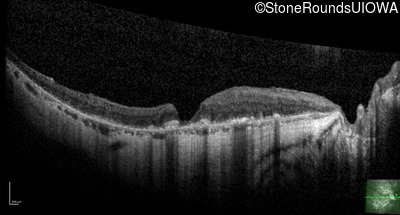

Optical Coherence Tomography - Right - 20/25 -1

Exemplar / OCT Stack